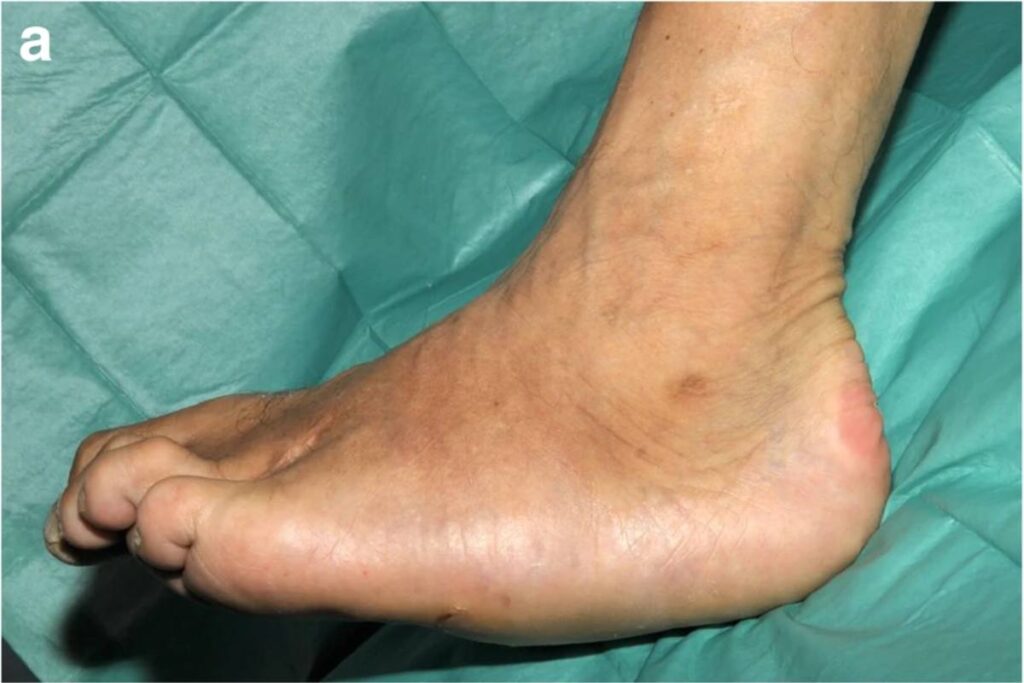

Imagens clínicas e de radiografias demonstrando um paciente com Artropatia de Charcot. Fonte: DOI: 10.1186/s13244-019-0768-9

Essas deformidades fazem com que o paciente tenha dificuldade de encontrar calçados e também são responsáveis por gerarem úlceras na planta dos pés. Essas úlceras são resultantes de pontos de hiperpressão na planta dos pés gerados pela deformidade do pé.

Seus sintomas iniciais são o inchaço, vermelhidão e aumento de temperatura do pé e após o surgimento dos sintomas os pés começam a se deformar. Com a deformidade surgem feridas. Essas, quando complicadas com infecção profunda, podem determinar a necessidade de amputações parciais ou totais do pé.